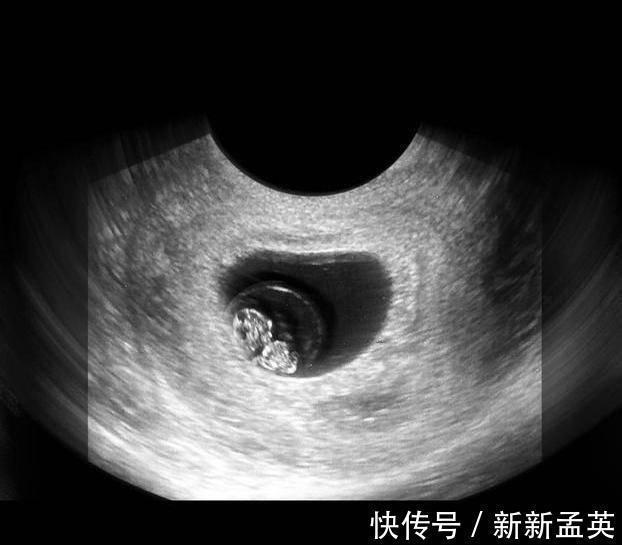

此时的胎儿继续快速发育,器官已经不是模糊一片,而是具有了鲜明的特征,比如手指脚趾已经形成,耳朵和牙齿也在发育,消化器官也开始发育了,基本都在定向地发展。

此时的宝宝可以叫做胎宝宝了,因为它已经具备很多人类的特征了,他的各个器官、肌肉和神经系统已经发育的产不多了,顾家也开始越来越坚固,从图片上看,宝宝就是迷你型的胎儿,他的各个器官开始工作了。